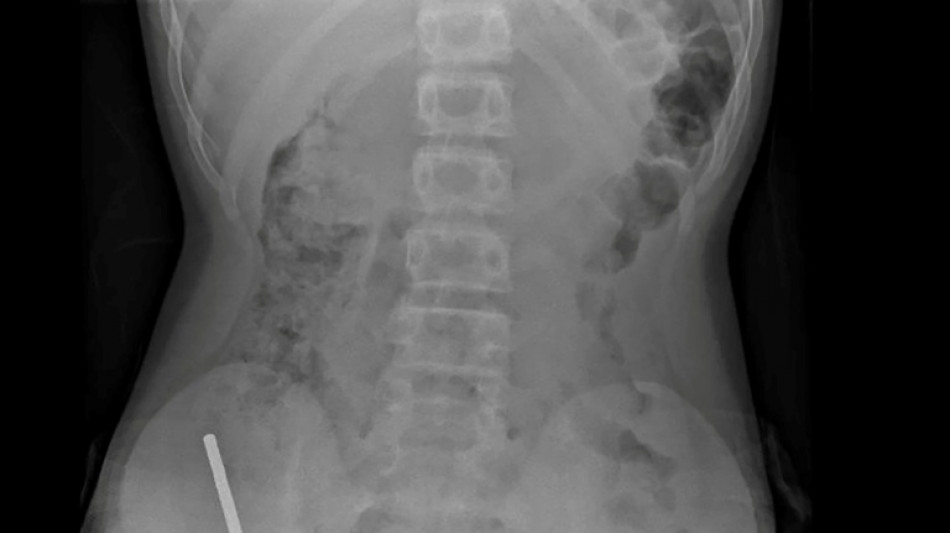

Nouvelle-Zélande: un adolescent opéré après avoir ingéré près de 100 aimants achetés sur Temu / Photo: Handout - NEW ZEALAND MEDICAL JOURNAL (NZMDJ)/AFP

En Nouvelle-Zélande, un adolescent de 13 ans s'est vu retirer plusieurs parties nécrosées de ses intestins après avoir avalé près d'une centaine d'aimants achetés en ligne sur le site Temu, a rapporté vendredi une revue médicale.

"Il avoué avoir ingéré entre 80 et 100 aimants puissants au néodyme, de 5x2mm environ, une semaine plus tôt", indique un rapport des médecins de l'hôpital de cet hôpital, publié dans le New Zealand Medical Journal (NZMJ).

Les médecins ont déclaré que la pression exercée par les aimants avait provoqué une nécrose dans quatre zones de l'intestin grêle et du gros intestin du garçon.

Il a été opéré afin que l'on lui retire les aimants et les tissus nécrosés, et il a pu rentrer chez lui après huit jours à l'hôpital.